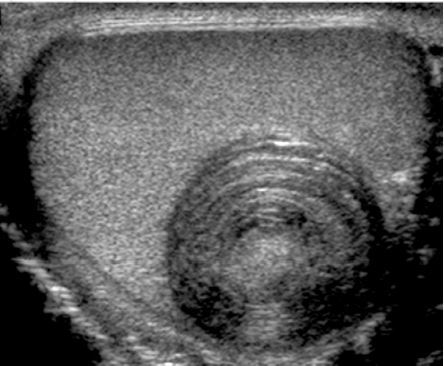

Testicular epidermoid cyst

• benign germ cell neoplasm

• monodermal teratoma - only ectodermal components

• appearance

• well-marginated lesoins that are typically hypoechoic

• hyperechoic rim with complete or partial rim of calcification

• onion ring/peel appearance